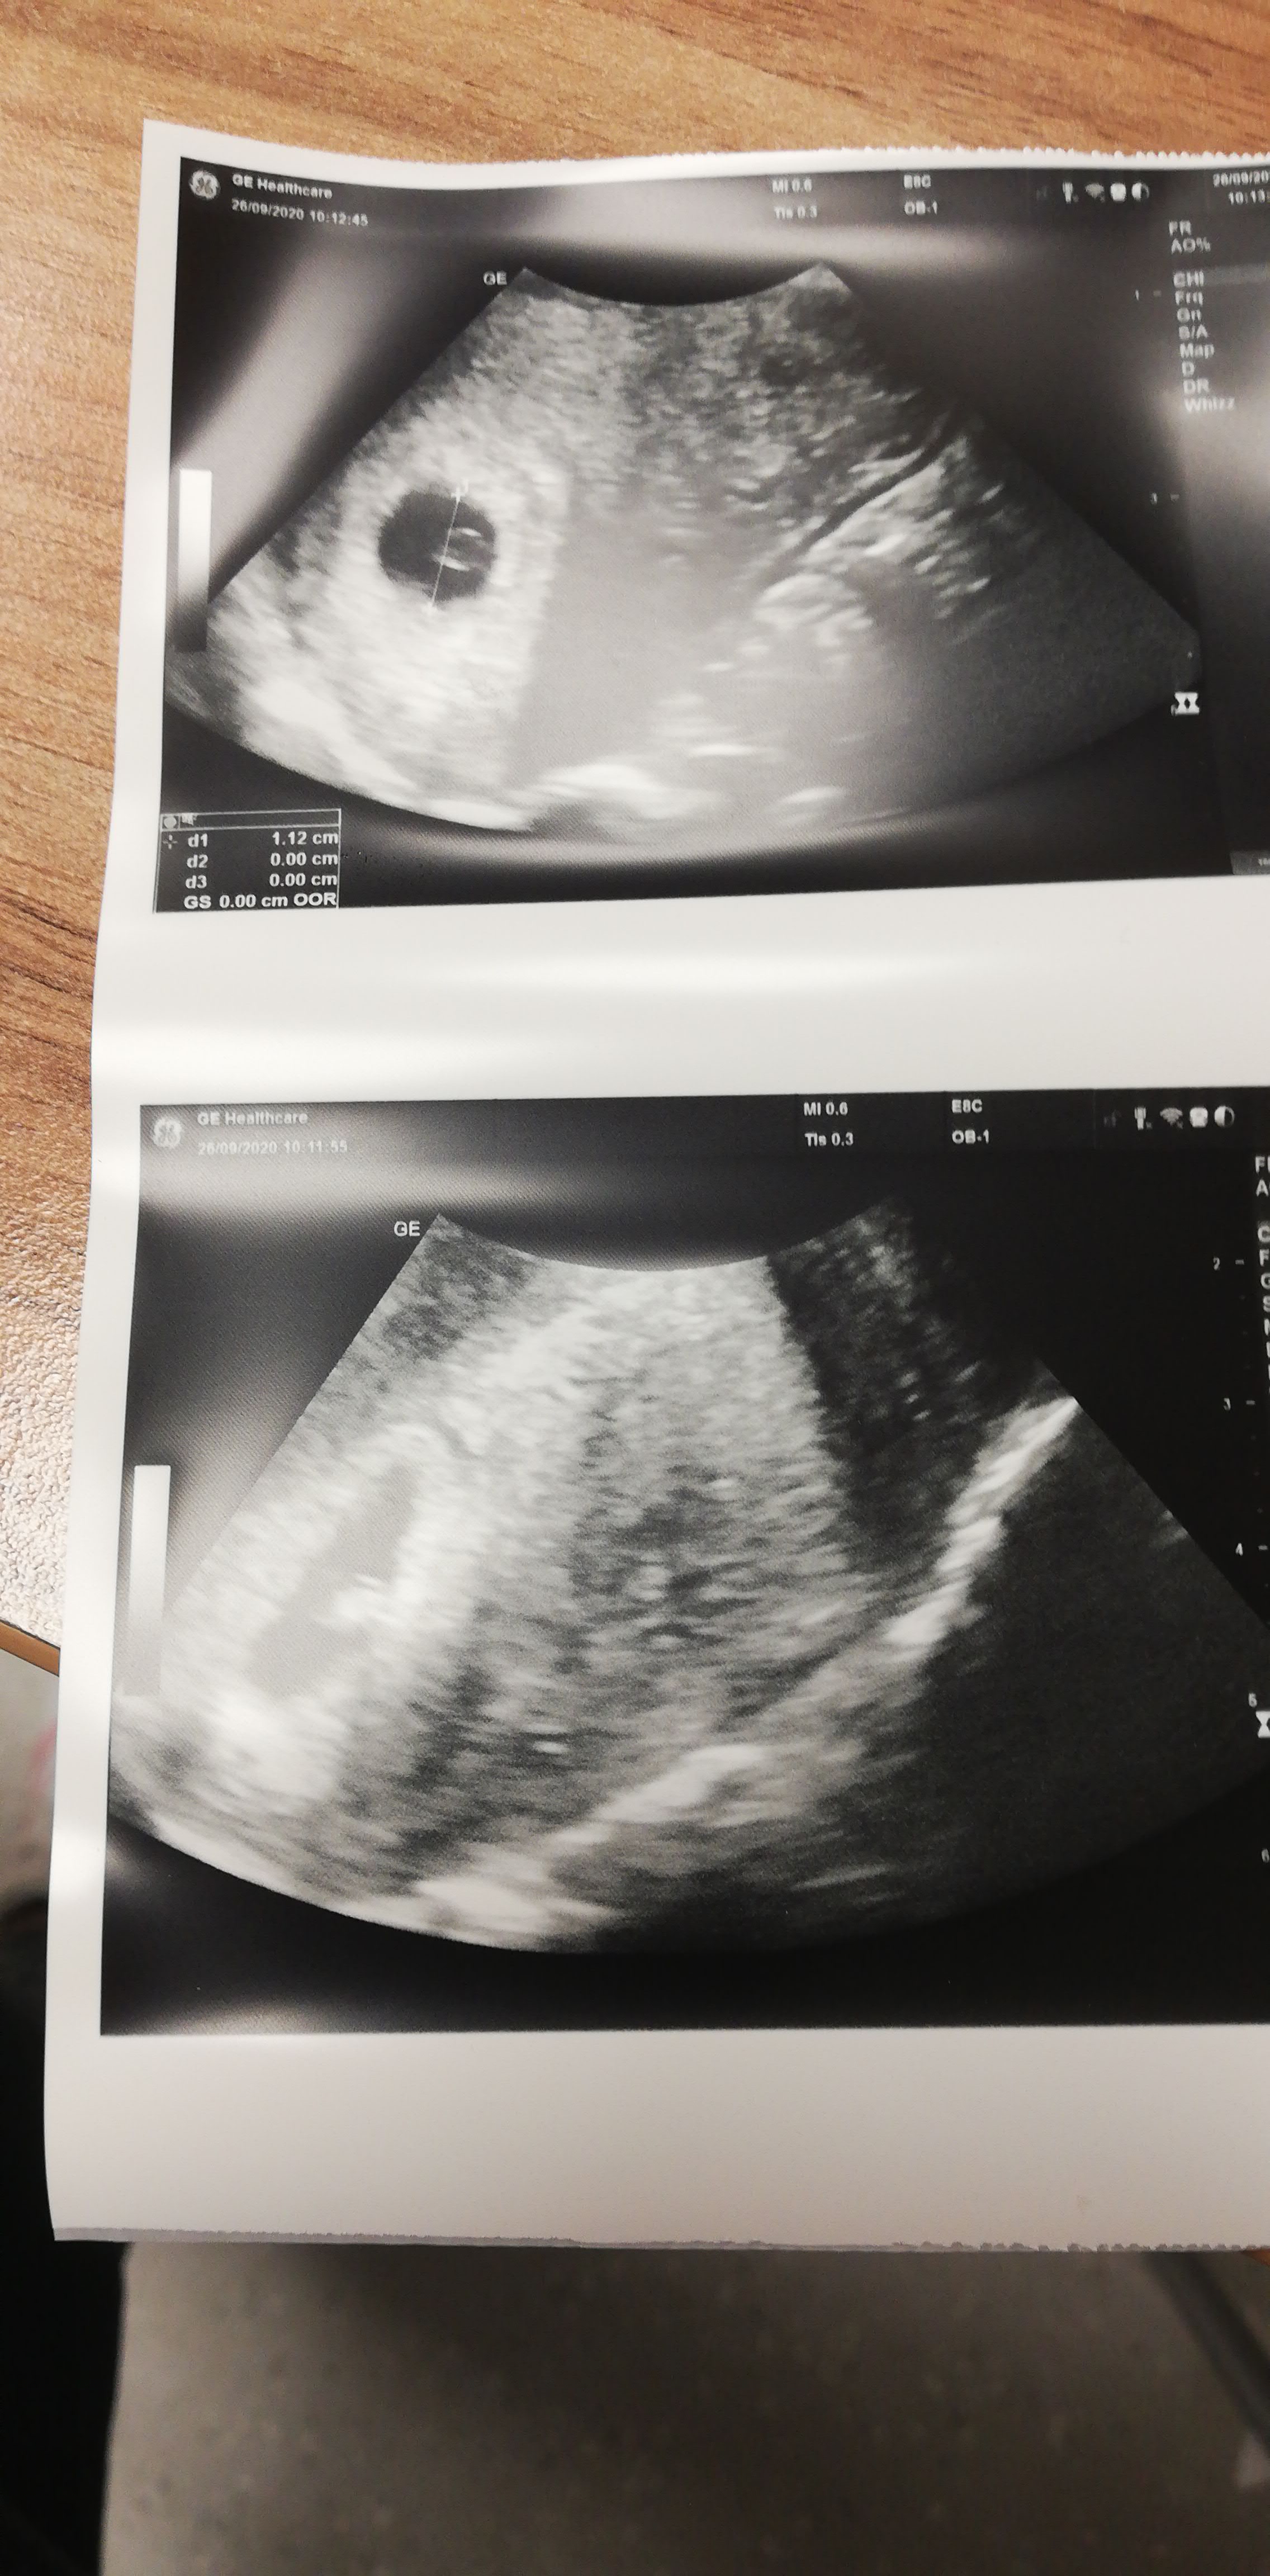

Dziewczyny mnie cos zaraz trafi, mój lekarz na nfz stiwrdzil że pęcherzyk jest za mały, w dniu usg był 6t1d, aż depresji dostaje, możecie na swoje oko coś ocenić? :( dodaje jeszcze jedno zdjęcie usg. Ostatnia miesiączka 14.08

A może miałaś późno owulacje i ciaza jest młodsza na usg. Nic o tym nie wspomnial? Ja w 5t2d miałam 1,14cm. Ale jest uwidocznione ciałko żółte to powinien pojawić się zarodek ❤, kiedy masz następna wizytę? Będzie dobrze